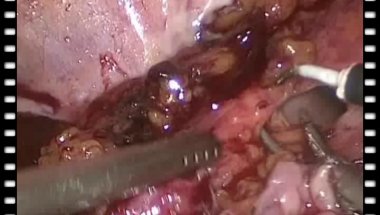

Гулиев Бахман Гидаятович

д.м.н., проф., руководитель урологического отделения Мариинской больницы

Гулиев Б.Г. - Лапароскопическая пластика протяженного дефекта прилоханочного отдела правого мочеточника туб.сегментом тонкой кишки

06 мая 2019

195

0